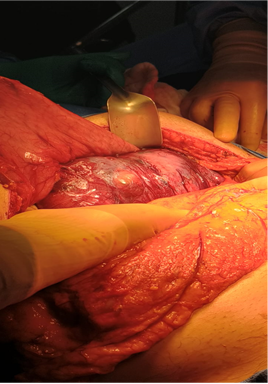

During surgery, a subserous, large exophytic tumor was found, affecting the posterior gastric wall of the body and fundus in the upper third. The tumor growth was mainly outside the gastric wall, and the bottom of the mass was closely adhered to the upper and anterior border of the pancreas and the spleen, so a splenectomy had to be performed. The tumor could be completely removed, (Figures 2&3) resected along with the gastric wall, preserving gastric wall edges without apparent tumor throughout the periphery. After the gastric reconstruction, a gallbladder resection was performed while the histopathologic report of the borders of the gastric wall was available. The histopathological report of the edges of the tumor in the gastric wall was reported as margins free of tumor. Therefore, despite the large resection, a gastric tube was constructed in the upper third of the stomach, being able to preserve part of the gastric body and the antrum.